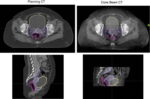

Early radiotherapy treatments were limited, to a degree, by the inability to reliably visualize the tumor before and during treatment. Initial localization of tumors was carried out using radiographic images of cross sections of the tumor center or anatomical center of the treatment site. With conventional x-rays soft tissues such as tumors were difficult to distinguish and treatment planning was also carried out manually by trained individuals [2]. By the 1960’s treatment planning had progressed slightly to include radiographic images and 2-dimensional planning. The 1970’s saw one of the biggest changes in treatment planning and thus treatment accuracy as high-speed fan-beam diagnostic computed tomography (CT) became more widely used [3]. Patient-specific three-dimensional treatment planning arrived and dose escalation and side effect reduction were possible with better dose conformity.

Historically, treatment planning relied on pre-treatment two-dimensional (2-D) imaging using the radiotherapy beam, with additional margins added around the target to compensate for anatomical changes. While this ensured tumor coverage, it also resulted in unnecessary irradiation of healthy tissue [4]. Using a high-energy radiotherapy beam as an imaging source produced very low-contrast images that were difficult to interpret. Helical tomotherapy, the first 3-D image-guided treatment technique, pioneered a CT-scanner gantry configuration to both deliver radiation and lower the beam energy for imaging and to improve tissue contrast with CT reconstruction [5].

In response conventional radiotherapy units began being equipped with flat-panel image systems that could provide a volumetric CT scan with a single slow rotation around the patient. These systems were called cone-beam CT (CBCT) scanners and were also implemented to provide image-guidance during surgery. As pre-treatment imaging technology advanced, it became clear that patient anatomy and tumor geometry were more dynamic and complex than previously understood, with changes such as organ deformation, tumor shrinkage, and weight loss significantly impacting dose distribution. It should be noted that image-guidance with x-rays adds a small additional exposure to healthy tissue increasing patient risk for a future additional cancer slightly and, in some cases, the imaging dose should be incorporated into the total treatment dose [6].

What has greatly assisted the progression of online adaptive radiotherapy has been improvements in artificial intelligence, this has greatly decreased the amount of human time and resources needed to support this throughout a department. Adaptive radiotherapy is not only about the ability to visualize anatomy and tumors better but also the ability to rapidly and accurately plan treatments. Current treatment planning involves the use of medical imaging, usually CT scans, to obtain the patient’s anatomy, then designing customized beam arrangements, geometry, intensity and modulation during plan optimization [4]. With online ART the ability to do all of this whilst the patient is on the treatment bed awaiting treatment adds a level of pressure, requires additional training of multiple treatment staff and results in the patient being on the treatment couch for longer which impacts on daily workflow.